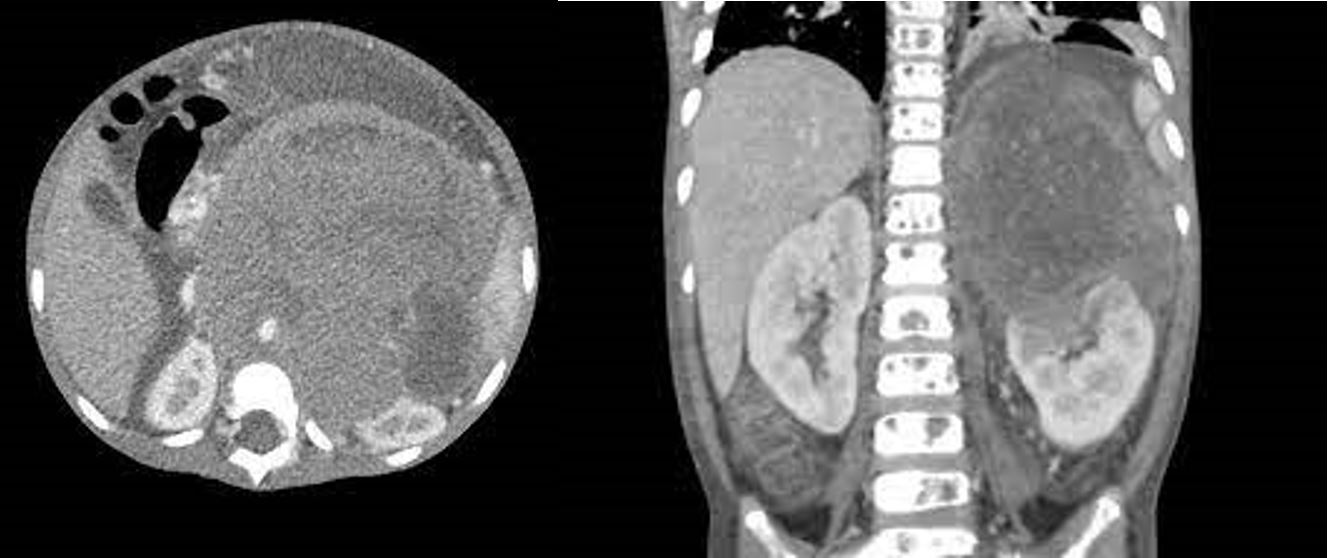

Để chẩn đoán u nguyên bào thần kinh, các bác sĩ sẽ thực hiện một số xét nghiệm và quan sát các triệu chứng của bệnh nhân. Các xét nghiệm này có thể bao gồm chụp cắt lớp vi tính (CT), chụp cộng hưởng từ (MRI), xét nghiệm máu và xét nghiệm thần kinh. Nếu có nghi ngờ về u nguyên bào thần kinh, bác sĩ có thể tiến hành thủ thuật lấy mẫu tế bào để xác định chẩn đoán.